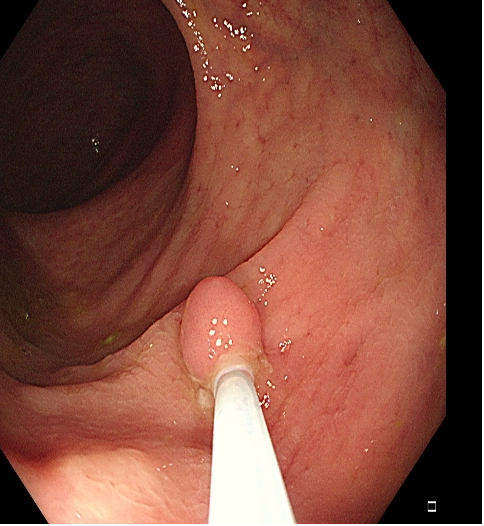

适用于≤5mm微小息肉的切除,但对 4~5 mm 息肉可能存在着切除不完全的问题。热活检在冷活检基础上,通过以高频电流,可以对残余病变灼除及对创面进行止血处理,但应注意避免电凝过度对肠壁浆膜层的损伤。

操作过程中应夹住息肉头端,适当上提(可避免损伤肌层),与肠壁保持适当距离,当息肉蒂部出现发白时,停止电凝,钳除病变。应注意是,切除息肉不易过大,否则会造成通电时间延长,增加全层损伤的风险(图1)。

图1 热活检钳除术示意图,A 钳除前,B 钳除后创面。C-D:热活检钳除术注意事项,息肉体积过大,增加电凝时间,造成透壁性损伤。